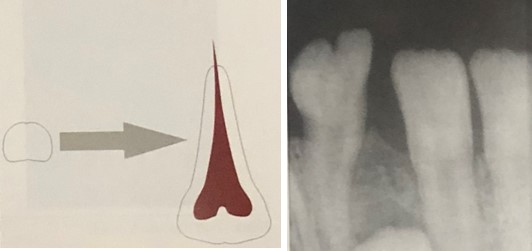

Essa condição é mais comum na dentição decídua e na região anterior. Importante observar que, nessa condição as coroas dos dentes fusionados normalmente parecem ser grandes e únicas podendo também ocorrer uma coroa bífida. Observem a Figura 1.

Já na geminação dental, em algum momento da odontogênese ocorreu a tentativa de um germe dentário em dividir-se, resultando em um dente com coroa bífida, ou seja, apenas uma raiz e um canal radicular em comum.

Uma de suas características importantes é que o esmalte ou a dentina pode ser hipoplásica ou hipocalcificada. Observem a Figura 2. Interessante salientar que no diagnóstico diferencial da geminação inclui a fusão.